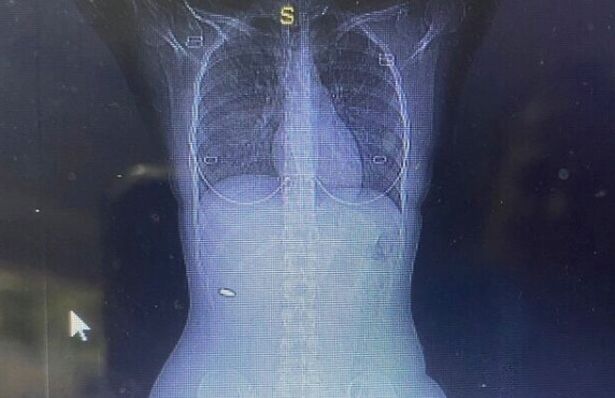

Theo như một cô gái Israel gần đây cảm thấy nhận ra sự việc bắt nguồn từ khi tới dự đám cưới một người bạn, khiến bị cơn đau dai dẳng hành hạ suốt 3 tháng cô gái đã tới bệnh viện chụp cắt lớp vi tính (CT), cho thấy có vật thể dạng kim loại gần cột sống .

Viên đạn nằm gần cột sống.

3 tháng sau, Bloy vẫn không ngừng cảm thấy đau đớn nên tới bệnh viện kiểm tra. Cô yêu cầu chụp ảnh cắt lớp vi tính (CT), cho thấy có vật thể dạng kim loại gần cột sống.

Sau khi tiến hành phẫu thuật gắp dị vật, các bác sĩ mới nhận ra đó là một viên đạn cỡ 5,56mm, chuyên dùng cho súng trường.

Bloy nói: “Tôi được cứu mạng bởi điều kì diệu. Các bác sĩ nói chỉ cần viên đạn xê dịch thêm vài cm nữa là tôi có thể bị tổn thương rất nặng”.